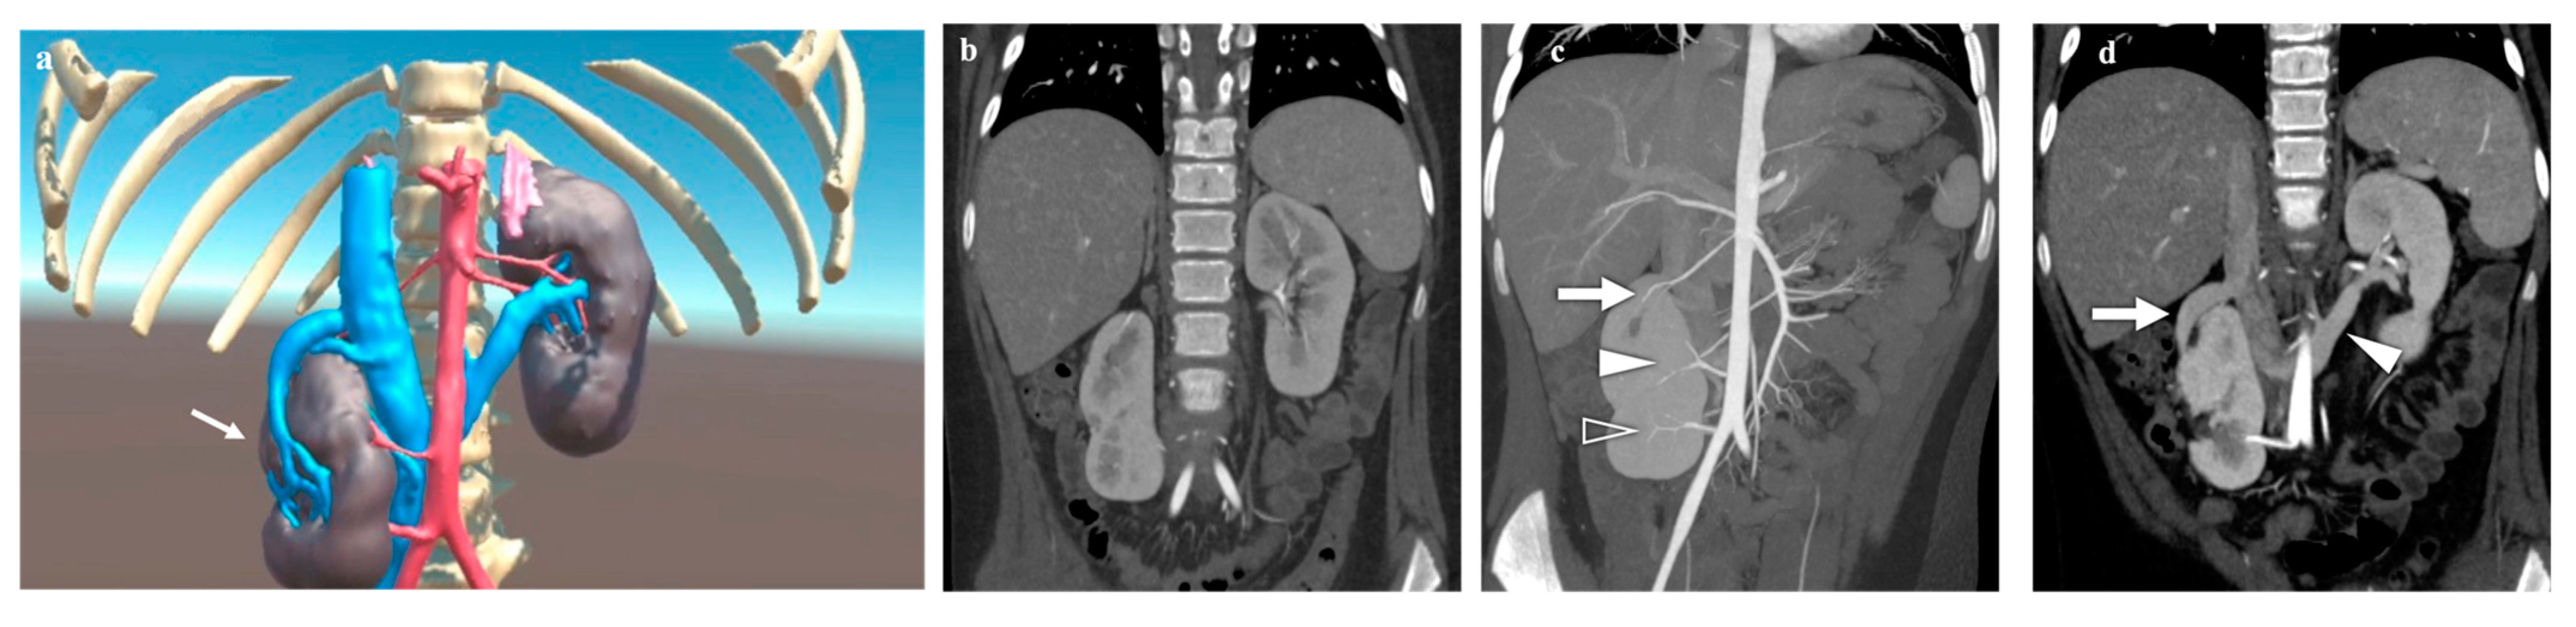

3.3. Kidney Lesions and Congenital Anomalies

| Case n. 6 | Female | 10 years | Ptotic and hypodysplastic kidney | Right |